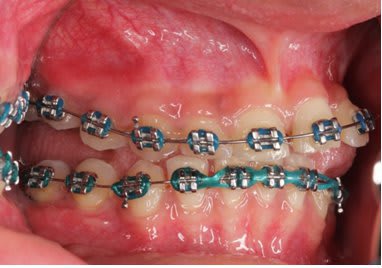

Et après environs un ans de traitement

Photo 1 on met des brackets et fils un ans plus tard Photo 2

Une seul possibilité a ma connaissance qui explique le canting antérieur et l'open bite postérieur.

Bingo

Il y avait ankylose de la 22 mais pas des molaires.

Sa se devine ici car le fil est quasiment droit ce qui signifie que sa forme c'est exprimé presque complètement.

Le problème étant que si la forme du fil est correct sa position ne l'est pas.

La 22 étant ankylosé elle a fonctionné comme un point d’appui et a fait bouger tout le reste.

Le fil rond pouvait tourner dans le slot de 22, vue qu'il n'y avait pas de dent en postérieure rien n’empêchait la rotation du fil et donc l’aggravation de la malocclusion.

La 21 qui était proche a était la plus affecté sa se voit bien sur les photo avec bracket, elle a subit une importante rotation dans le sens mesio distal et a était procliner. Son changement de position a eu un impacte sur 21 puis sur 11 ect ect , les effets devenant de plus en plus faible a mesure que l'on s'éloigne.

On a eu une important proclination de l'ensemble des incisive.

Mais encore une fois ce qu'il faut noter c'est le changement important au niveau de 21 avec un FIL PARFAITEMENT DROIT au niveau des incisives